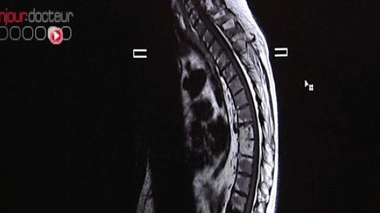

• Mal au dos

Mal au dos

Spondylarthrite ankylosante, la soudure osseuse des articulations